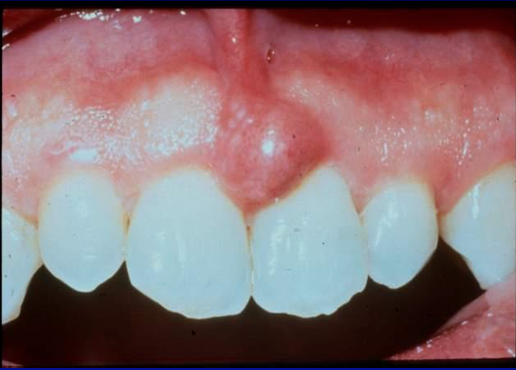

gingival abscess

localized purulent infection that involves the marginal gingiva or interdental papilla

etiology: acute inflammatory response to foreign substances forced into the gingiva

clinical features: localized swelling LIMITED to marginal gingiva or papilla. A red, smooth, shiny surface. May be painful and appear pointed. Purulent exudate may be present. No previous periodontal disease.